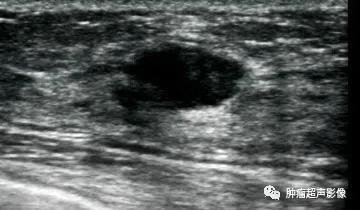

女33,病理证实腺肌上皮瘤,肿块边界清楚,形态规则,低回声,回声欠均匀,后方回声增强,无血流信号,呈现良性肿块特征。